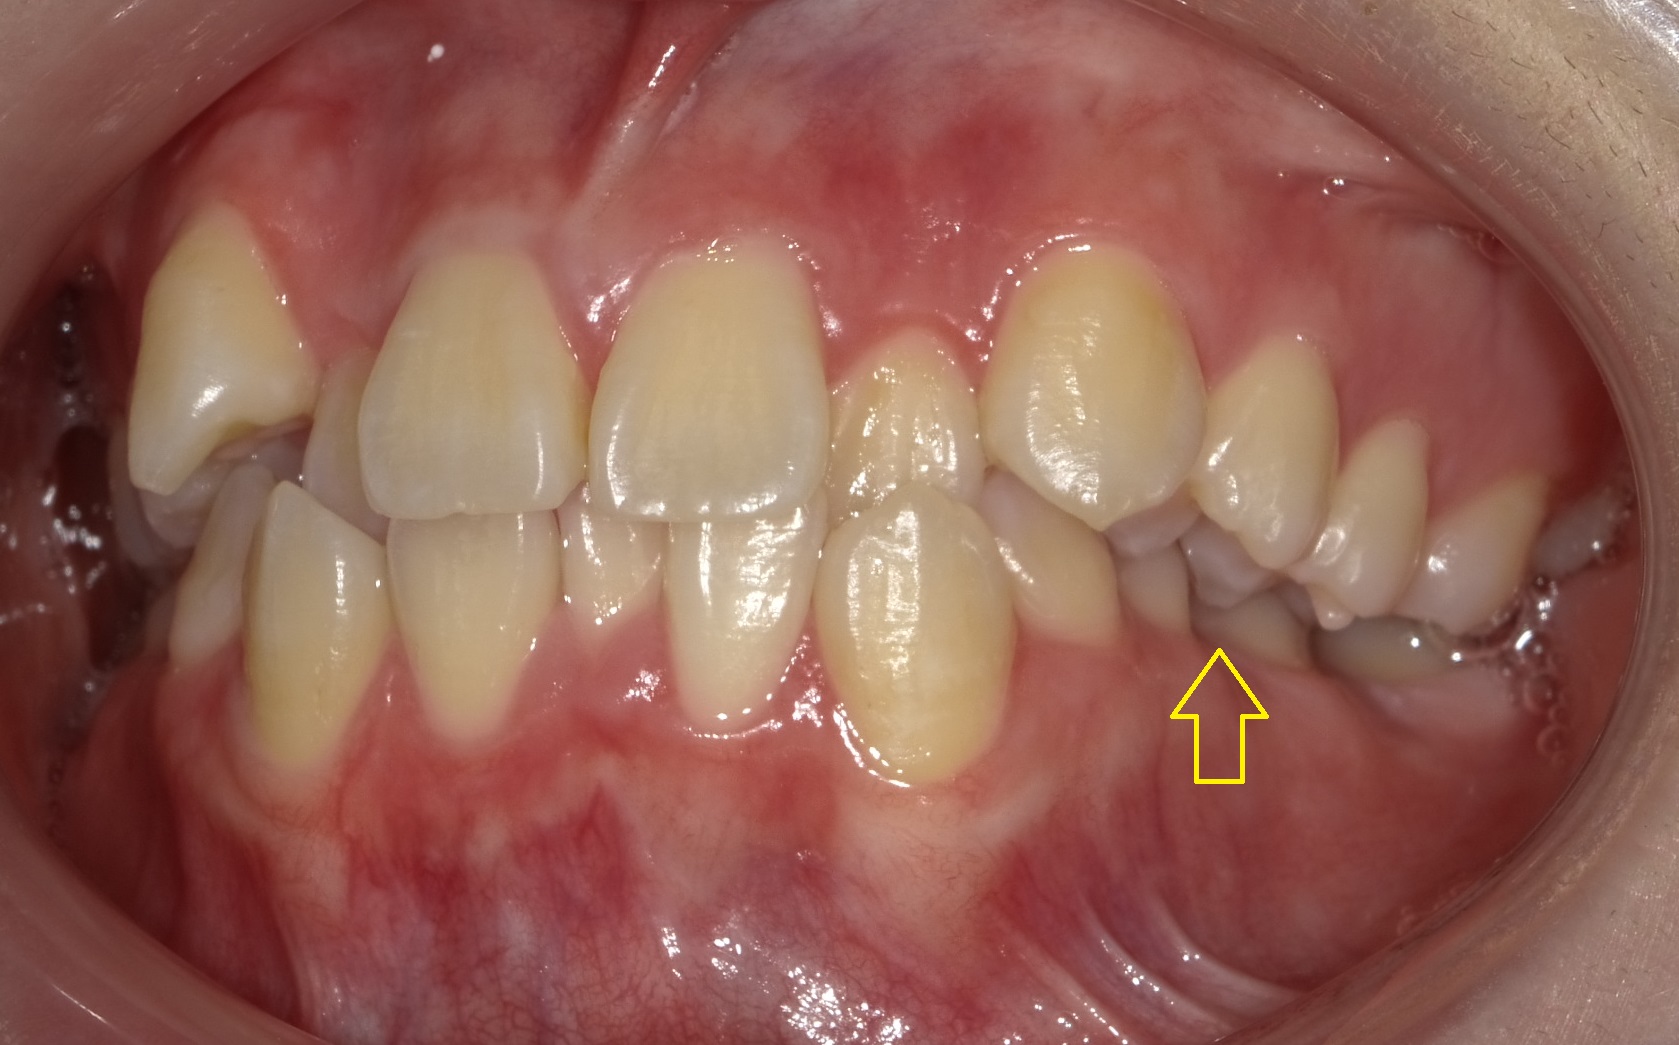

写真のとおり、①八重歯を目立ち、②上の2番目の歯が下の前歯に対して内側に傾いて、全体的にバラついているのですが、一番の問題は、

上の写真にあるとおり、左側がほぼ噛み合っていない点です。

この噛み合わせが原因で左右のバランスおよび顔の輪郭すら左右差が生じてきます。

右側の噛み合わせと比べるとその差は歴然です。